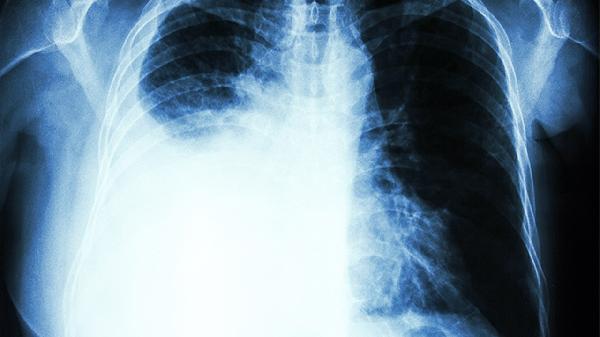

5、胸膜炎

肺部感染或结核等疾病可能累及胸膜,引发左侧肋骨下刺痛,深呼吸时加剧。需根据病因使用阿莫西林克拉维酸钾片抗感染,或异烟肼片抗结核治疗。治疗期间应卧床休息,监测体温变化。